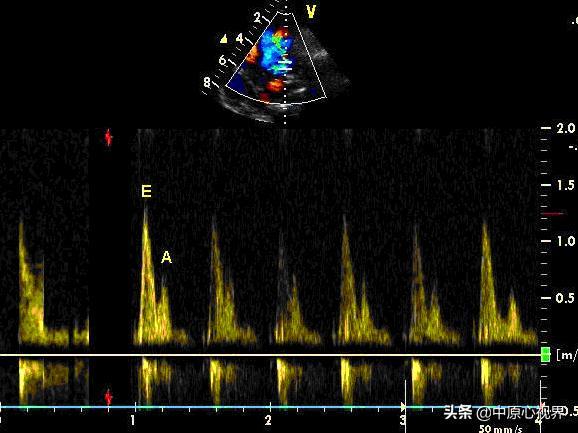

心功能评估还包括舒张功能的测定。E峰与A峰比值(E/A)是一个重要指标,正常情况下应大于1。这个比值反映了左心室在舒张期的充盈情况,可以帮助医生判断是否存在舒张功能障碍。